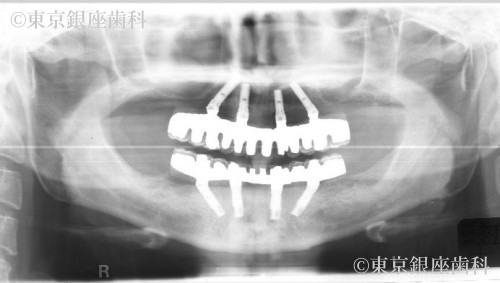

重度の歯周病によって失った審美性や機能性をワンデイインプラントによって改善した症例

何年間も歯科医院には通っておらず、全ての歯の揺れがひどく今にも抜けそうだったが金銭的な理由により一時保留にしていた。3年後に来院した際には、歯周病が悪化し著しい歯の揺れ、骨の吸収が見られた。そして左上の前歯が自然脱落した。

歯周病の進行により歯に動揺があり長期の保存が難しくこのままでは予後が不安であった為全顎的な治療が必要と判断。上下全ての歯を抜歯。重度の歯周病により骨が吸収されているため、上顎骨が薄く左側は上顎洞に骨を足す治療(サイナスリフト)を行い上顎に4本、下顎に4本のインプラントを埋入しワンデイインプラントを行った。現在半年メンテナンス。

抜歯即時埋入でインプラント治療を行い、その日のうちに仮歯を入れて短期間での大幅な審美、機能の回復をした。また上顎骨が薄くインプラント埋入の難しい部位には人口骨を足しインプラント埋入を可能にした。